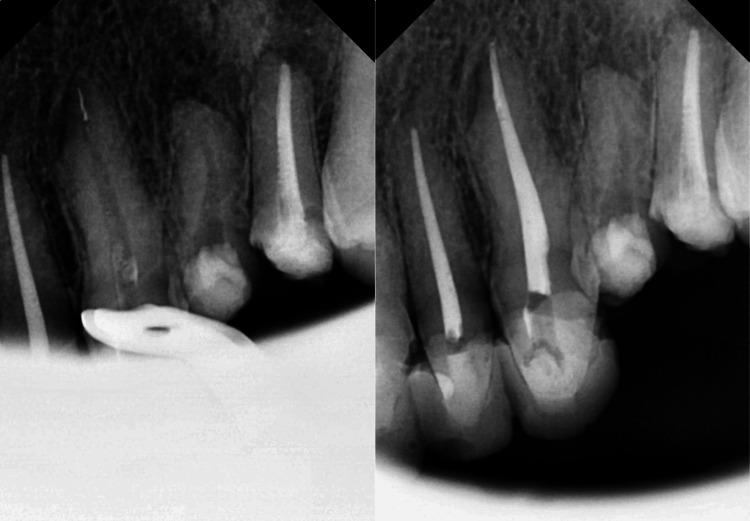

Aim This study aimed to evaluate the frequency of fractures in a new single-file reciprocating system used by endodontists. Methods Reciprocal systems were used to evaluate endodontist-treated patients' periapical radiographs and dental records. For the study, the kind of tooth, the quantity of root canals completed, the quantity of broken instruments, and the fragment's size were all recorded. A fracture risk calculation was made for every kind of tooth, root canal, and root third. The new reciprocating systems' fracture incidence was compared at a 5% significant level using the chi-squared test varied between 2 and 6 mm. Results There were a total of 5,066 root canals (2,128 teeth) from 1,818 patients. In single-file reciprocating systems, the incidence of fractured files relative to the number of instrumented canals was 22 (0.43%). The mesiobuccal root canal of mandibular molars and maxillary molars had the greatest breakage rates, which were 7 (36%) and 6 (27%), respectively. Conclusion The incidence of instrument fractures was lowered when linked to the usage of the Premium Blue reciprocating system in endodontic therapy.

目的 本研究旨在评估牙髓病医生使用的一种新型单根管往复式系统中器械折断的频率。方法 使用往复式系统评估接受牙髓病医生治疗的患者的根尖片和牙科记录。在研究中,记录了牙齿类型、完成的根管数量、折断器械的数量以及碎片大小。对每种牙齿、根管和牙根三分之一进行骨折风险计算。使用卡方检验在5%的显著水平下比较新型往复式系统的骨折发生率,其范围在2至6毫米之间。结果 共有来自1818名患者的5066个根管(2128颗牙齿)。在单根管往复式系统中,相对于预备的根管数量,器械折断的发生率为22例(0.43%)。下颌磨牙和上颌磨牙的近中颊根管折断率最高,分别为7例(36%)和6例(27%)。结论 在牙髓治疗中,与使用Premium Blue往复式系统相关时,器械折断的发生率降低。